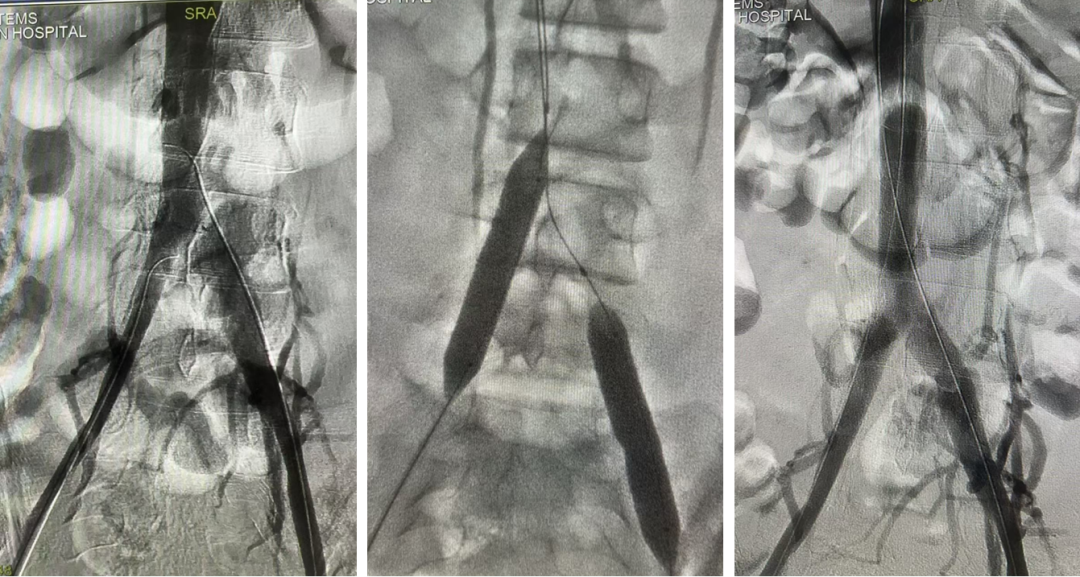

★ Case4:慢性IVCT腔髂静脉治疗

女,54岁

2024年10月22日坠落骨盆骨折,2024年11月7日置入下腔静脉滤器,11月8日手术。

2025年1月17日当地医院滤器取出术中发现下腔静脉髂静脉血栓放弃取出

图:第一次:扩张下腔静脉、髂静脉并取出滤器2025.2.13

图:二次复查CT并进行球囊扩张2025.3.31

图:早期复查结果比较满意(一年期通畅率>70%)